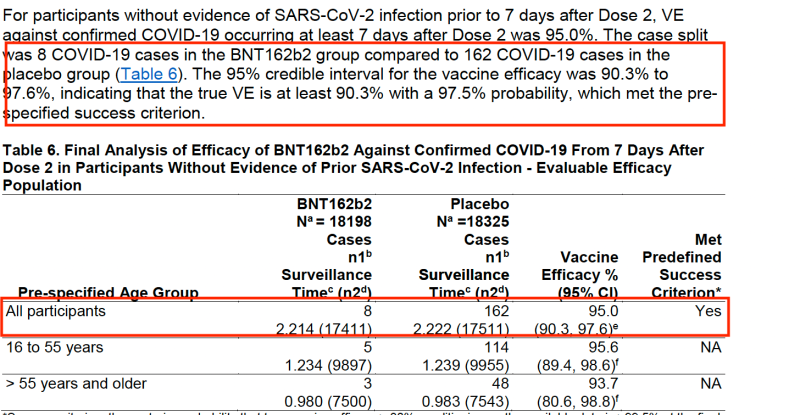

The 95% VE (vaccine efficacy) arises from the 8 confirmed Covid cases from the vaccinated group (from at least 7 days after Dose 2) compared to 162 from the placebo group. These two data points are essentially what Pfizer hang their hat on to prove their vaccine was a success.

This is the data that the FDA and other regulatory bodies around the world relied upon to grant EUA (Emergency Use Authorisation) for the Pfizer-BioNTech COVID-19 vaccine and for billions of doses to be shipped around the world with some countries enforcing highly controversial draconian vaccine mandates.